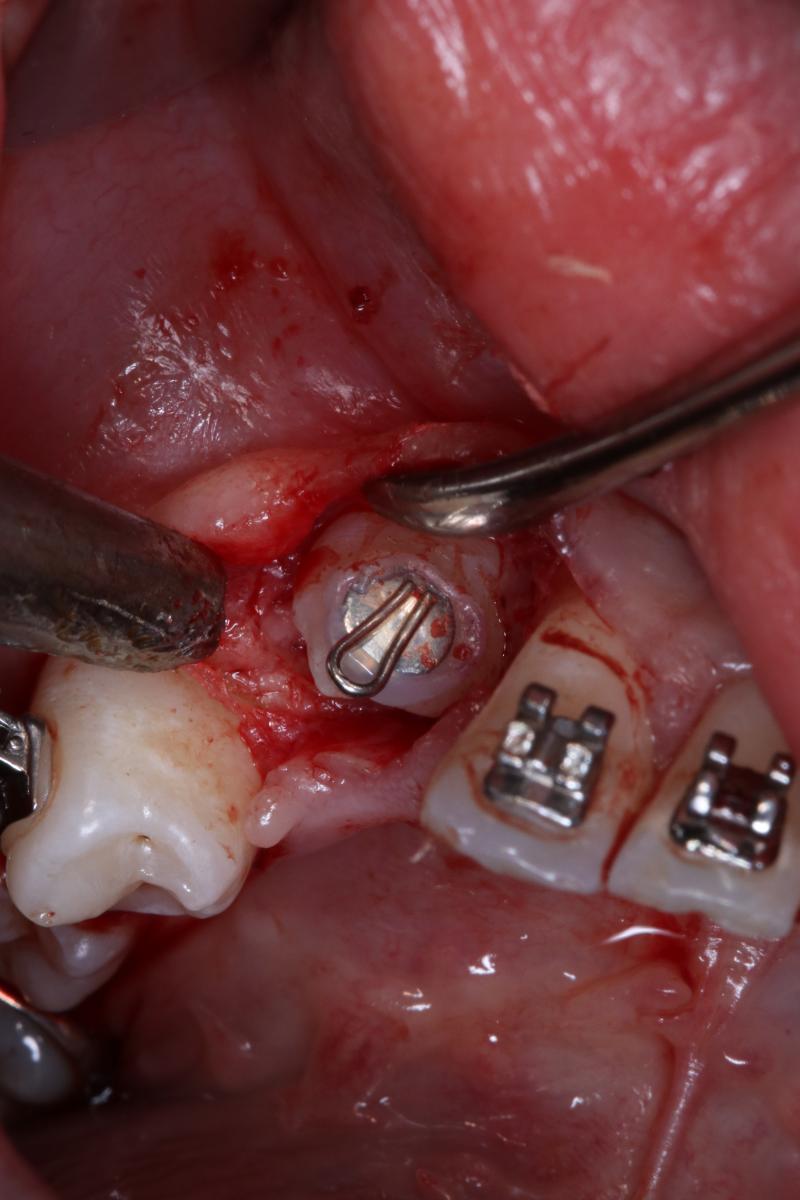

Kontaktujte násUkázky pracíOrtodontická expozice

Náš zkušený stomatochirurgický tým se postará o ortodontickou expozici požadovaného zubu.